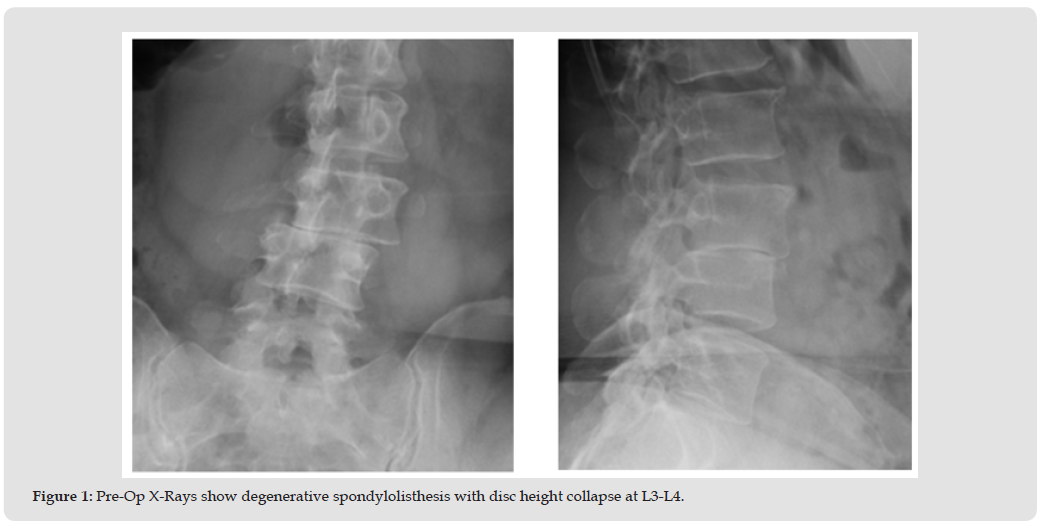

At the 3-month follow-up radiographs showed the instrumentation intact and in good position (Figure 2). Clinically the patients’ pain symptoms had improved dramatically (VAS Back-1.4/10, VAS Right Leg-0.4/10, VAS Left Leg-0.9/10, ODI -50%) and the patient continued physical therapy. CT scans were obtained at the next follow- up (8.2 months) due to a moderate increase in pain symptoms (VAS Back-6.0/10, VAS Right Leg-7.6/10, VAS Left Leg-1.0/10, ODI- 34%) as a result of increased activity and reduction of pain medication however the ODI had improved to moderate disability. The CT scans exhibited early and complete interbody and posterolateral fusion success (Figure 3). By the 1-year follow-up the symptoms had mostly resolved with minor residual back pain and complete resolution of radicular pain (VAS Back-2.0/10, VAS Right Leg-0/10, VAS Left Leg-0/10, ODI-26%) with a clinically significant improvement of 22 points from pre-op in the ODI. CT Scans taken at 1 year confirm complete fusion in both the interbody and posterolateral constructs seen previously (Figure 4).

The bone graft used for this case (Catalyst) was selected based on its handling and performance characteristics in a wide range of patients, most of which had multiple risk factors for failure. [11-13] Of particular interest with this case was fusion success in both the interbody and posterolateral constructs at 8 months in an active smoker, demonstrating rapid bone formation consistent with the dual pathways of both endochondral and intramembranous ossification. [9,10] This supports the versatility of Catalyst Bone Graft as an effective bone graft substitute in challenging patients. The combination of surgeon skill and experience in selecting the most appropriate and effective surgical procedures and adjuncts, including the choice of bone graft, resulted in a positive clinical outcome in this patient.